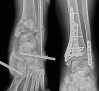

Case summary: We report a very rare injury of closed TTD with a follow-up period of 36 mo. Initial closed reduction was not successful because of a fractured highly unstable medial malleolus displaced into the ankle mortise, blocking the relocation of the talus. The patient was able to walk pain-free after the 3rd month of surgery. At the 36-mo follow-up, there were 10 degrees of flexion loss and 10 degrees of extension loss in the tibiotalar joint. Furthermore, 5 degrees of subtalar joint inversion-eversion loss was present.